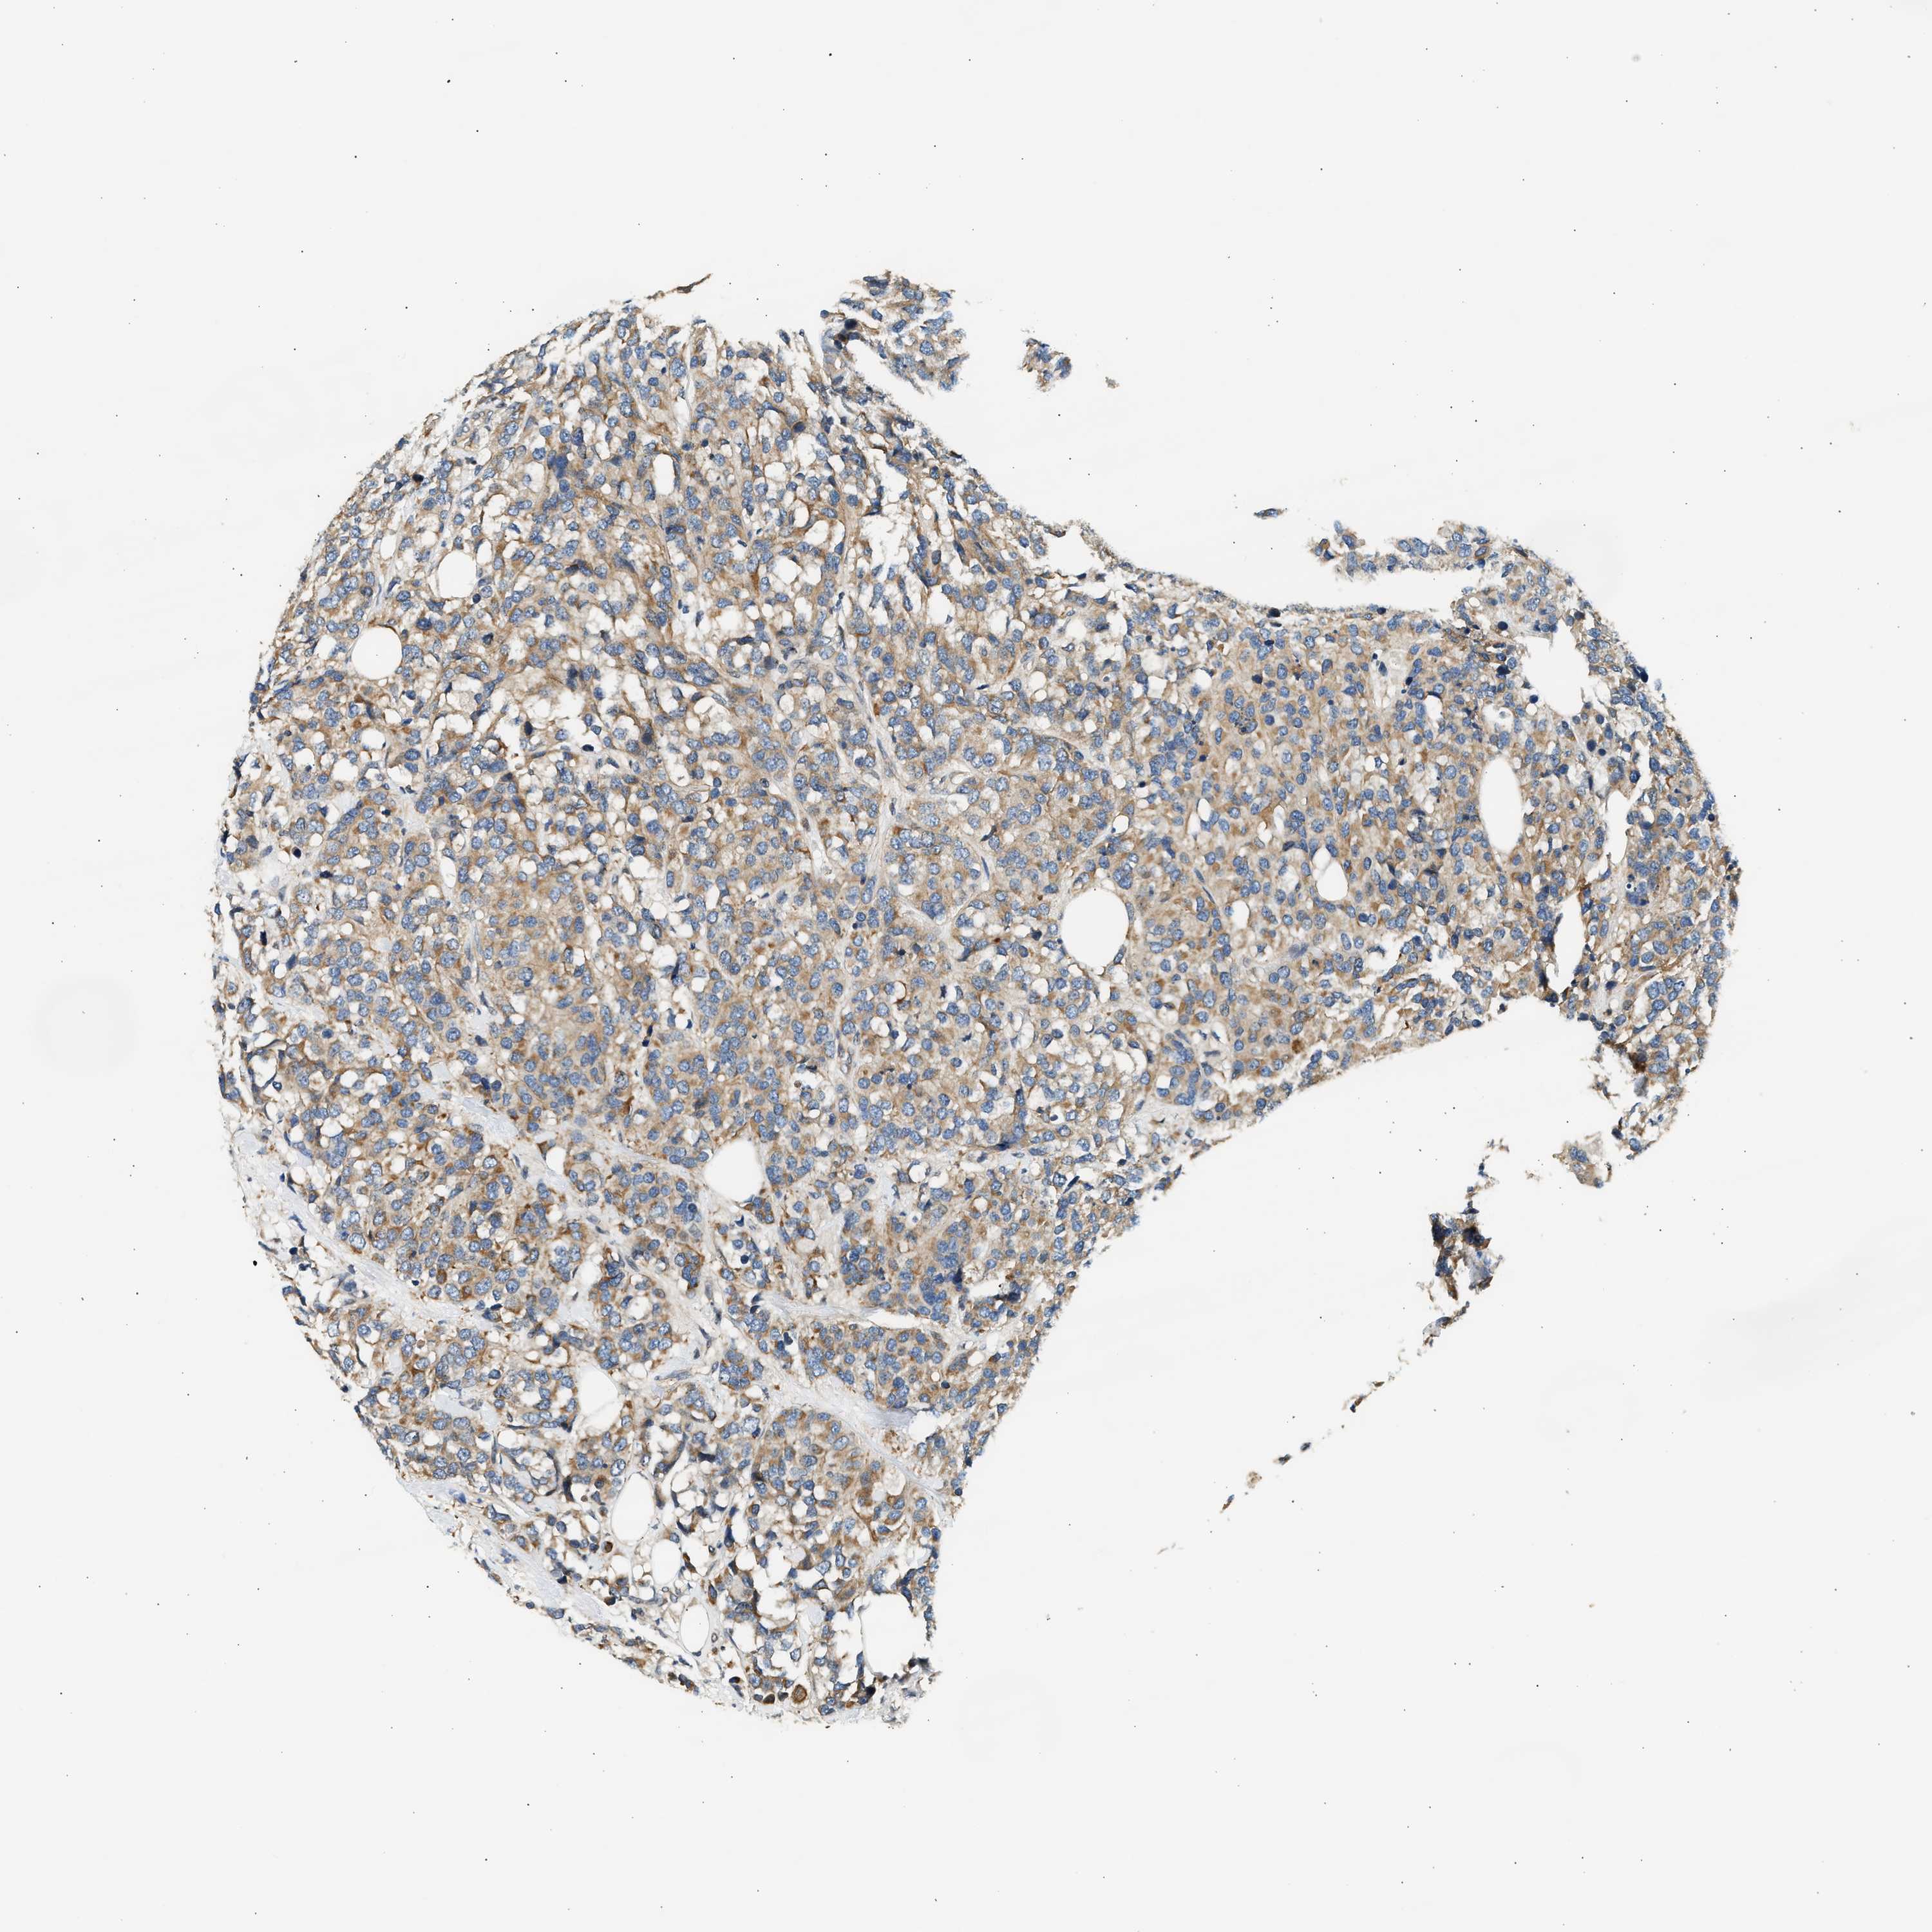

CANCER BREAST CANCER Show tissue menu

BRCA TCGA BRCA VALIDATION PROTEIN EXPRESSION

Breast cancer

Human cancer